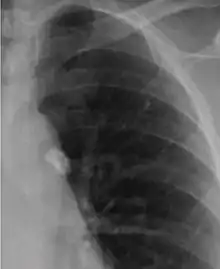

Chest X-ray of a Ghon's focus

It is a small area of granulomatous inflammation, only detectable by chest X-ray if it calcifies or grows substantially (see tuberculosis radiology).[2] Typically these will heal, but in some cases, especially in immunosuppressed patients, it will progress to miliary tuberculosis (so named due to the granulomas resembling millet seeds on a chest X-ray).[2]